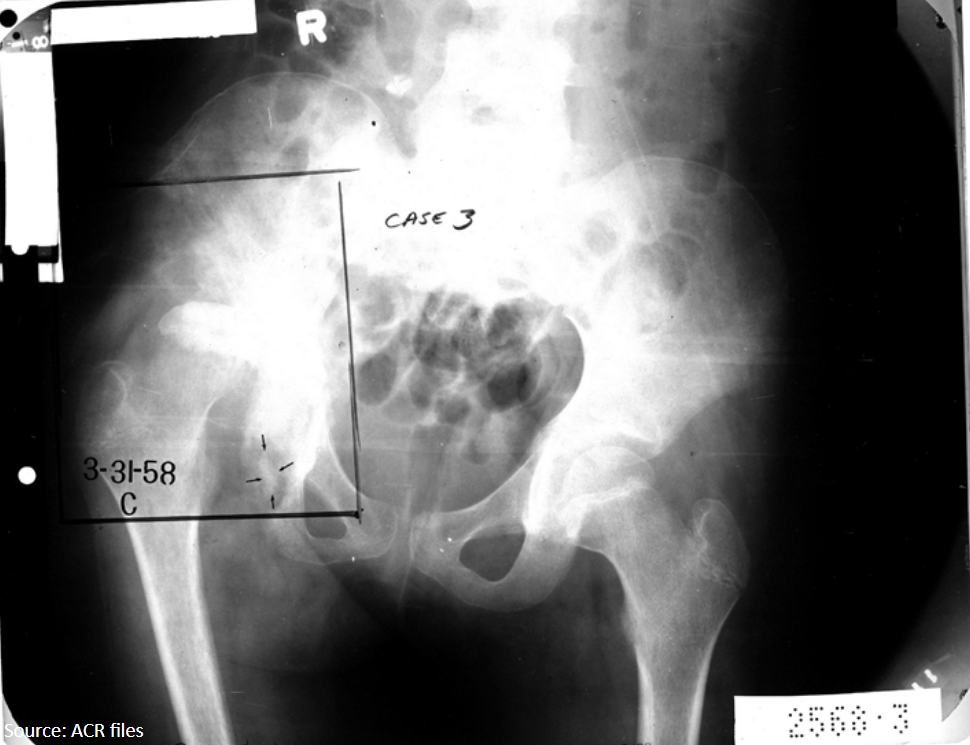

11

Q

What radiographic sign is present?

What does this mean by definition?

A

Waldenstrom’s sign: uneven hip joint space (one is increased) due to joint capsule swelling laterally displacing the femur

AVN of femoral capital epiphysis: LCP

12

12-year-old female presents with hip pain that refers to the knee.

Based on the evidence of avascular necrosis in her femoral capital epiphysis, what is the diagnosis?

Legg-Calve-Perthes (LCP)

Waldenstrom sign present

13

10-year-old female presents with a painful limp.

What is the diagnosis?

LCP

Legg-Calve-Perthes

sclerosis and flattening with epiphyseal fragmentation of femur (AVN)

14

What findings are seen in the right femur?

Mushroom deformity, degenerative changes, superolateral displacement of femoral head